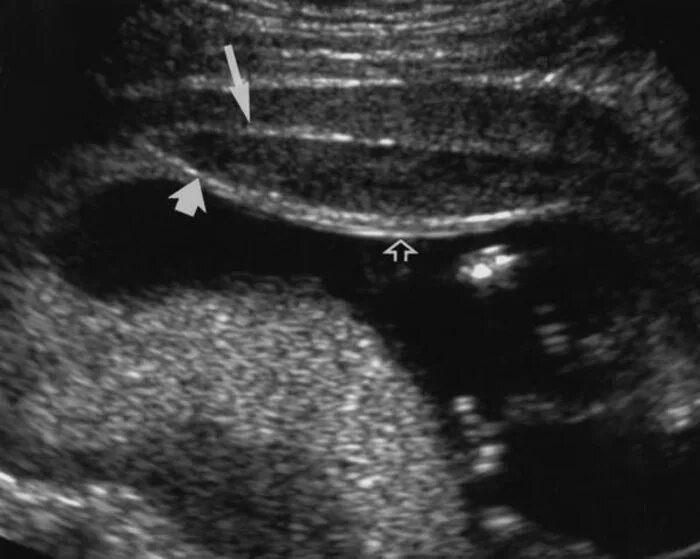

Как выходит гематома при беременности сроки